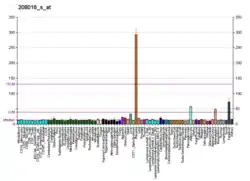

A huge number of polymorphisms is reported in the databases for AT1R which provide an avenue to explore these polymorphisms for their implications in protein structure, function and drug efficacy. Methods In the current study all the SNPs (10234) reported in NCBI were analyzed and SNPs which were important in protein structure and drug interactions were identified. Structures of these polymorphic forms were modeled and in silico drug interaction studies were carried out. Results Result of the interaction studies with polymorphism was in correlation with the reported case. Two SNP mutated structures of AT1R i.e. rs780860717 (G288T), rs868647200 (A182C) shows considerably less binding affinities in case of all angiotensin receptor blockers (ARBs).[14]